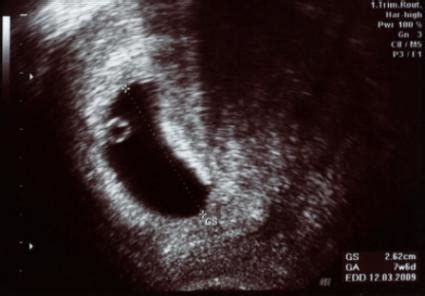

Recent comparative medical images showing the microscopic details of implantation are challenging those assumptions. These visuals reveal subtle vascular changes and cellular displacement invisible to the naked eye. The images show early embryo adhesion triggering subtle blood vessel shifts and minor tissue reactions—changes that precede visible spotting by days.

Image Gallery

[In the images, early implantation appears as fleeting faint color variation in the endometrial lining, accompanied by microtrauma to the surface—white blood cells reacting, minimal bleeding pathways forming.]